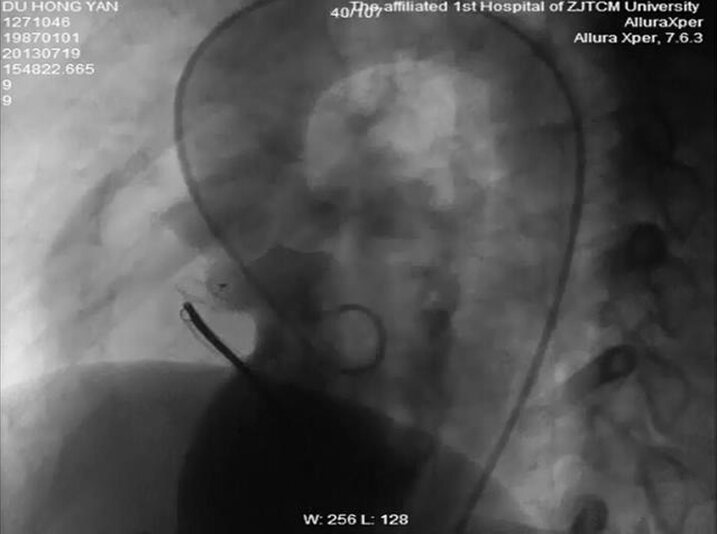

小陈很快被安排手术,在局部麻醉情况下,毛威教授和蔡宏文副主任医师开始实施“补心”手术。毛教授一边和小陈聊天,一边通过娴熟的血管穿刺和导管操作技术,利用外周血管建立了一条动静脉轨道,通过这条轨道将一把折叠的“小伞”缓缓送入心脏,从X线影像上,能够清楚地看到这把“小伞”很快抵达心脏并穿过室间隔的漏洞,随着精细的心内导管操作,折叠的“小伞”慢慢滑出伞柄(输送鞘管)并撑开,随着心脏的跳动,“小伞”精准地与漏洞的两边贴合在一起,重复造影,漏洞被堵住了。毛威教授指着屏幕上的“小伞”说,它叫封堵器,是由可以变形的记忆合金铸造,它暴露在血液里就会自动恢复形状,成为两个圆形伞罩,中间由一根细腰连着,刚好把室间隔缺损口的两边堵住,就好比一把小伞,堵住了小陈心中的缺憾,再过两三个月,心脏里的上皮组织就会慢慢爬满封堵器,封堵器也将与小陈的心脏整整融为一体。

室间隔缺损封堵术后造影图:分流消失